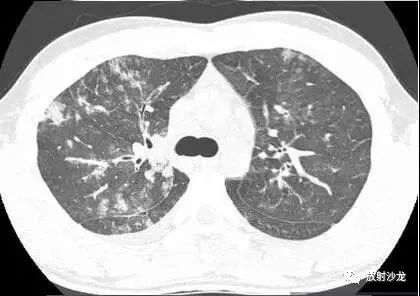

一名21岁男因发热咳嗽一周就诊。影像学结果检查如下:

胸部CT(图1-3)显示,支气管壁增厚,小叶中央型结节,磨玻璃影或小叶实变,轴向间质和小叶间隔增厚,以及双侧少量胸腔积液。胸片(图4)显示弥漫性斑片状或结节状磨玻璃影,线性阴影,以及双侧少量胸腔积液。

最终诊断:肺炎支原体肺炎

X线片上最常见的表现是高密度影,节段性或非节段性分布。CT上,最常见的是支气管壁增厚(81%),其次是小叶中央型结节(78%),磨玻璃影(78%)和小叶实变(61%)。轴向间质及小叶间隔增厚常见。胸片中通常很难鉴别肺炎,但在高分辨CT中可见。其它表现是胸腔积液和淋巴结肿大。成人CT中常表现为细菌性支气管肺炎和病毒性间质性肺炎的合并感染。但儿童肺炎支原体肺炎与细菌性大叶性肺炎相似。